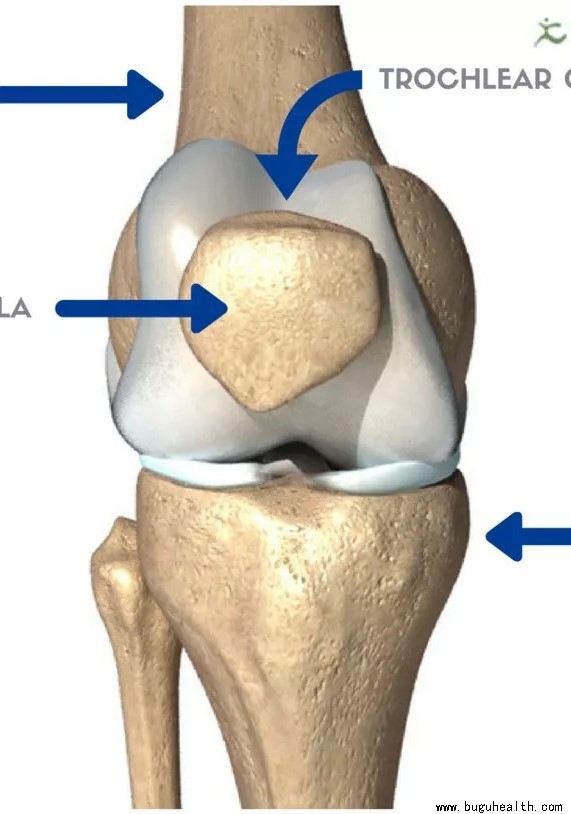

- 很多人都知道前交叉韧带(ACL)撕裂时,会听到膝盖处“砰“的一声响。但殊不知相当一部分的情况实际上是发生髌骨脱位。这类损伤的疼痛程度并不亚于ACL撕裂,毫无疑问,髌骨脱位也需要进行紧急处理,并需确定运动员重放赛场的最佳机会。可以说,髌骨脱位发生率可能远超人们的想象! .....

- 膝关节是我们身体中结构最复杂、最大,受杠杆作用力最强的一个关节,起着承重、传明递载荷的作用。膝关节主要是屈伸运动,在屈曲位兼有旋转,同时有很小范围的内外翻被动活动。膝关节包括由股骨下端和胫骨上端构成的胫股关节,以及由髌骨和股骨滑车构成的膑股关节。膝关节的关节囊及韧带起到保护及稳定关节的重要作用。在膝.....

- 膝关节屈伸活动时膝盖后方的疼痛,在上下楼、下蹲、爬山、搬重物尤为明显,或者用手按压髌骨摩擦推动,感觉到关节里面“沙沙”响,那您就要考虑您是否出现了“髌骨软化”的问题了。膝关节的髌软骨软化症是一种发生在膝关节的髌骨软骨面的退行性改变(俗称的老化),是髌股关节软骨长期慢性磨损引起的。关节软骨会产生软化、.....